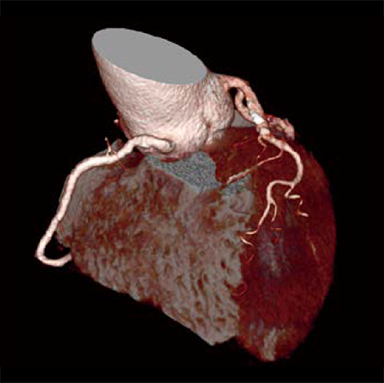

In cardiac CT examinations, the various factors such as heart rate and heart movement affect image quality. With conventional image reconstruction methods, unfocused coronary arteries and artifacts caused by motion could occur, resulting in images not meeting the expected quality, which could affect the diagnosis. To help resolve these problems, Fujifilm developed Cardio StillShot, which calculates the direction and amount of movement of the subject in four dimensions based on the raw data collected during cardiac CT examinations, and corrects it during image reconstruction to achieve an effective time resolution of 28 msec.*1 The effective time resolution contributes to improved diagnostic capability by providing high-definition focused clinical images with less motion artifacts even in patients with a high heart rate.

Cardio StillShot: OFF

ON